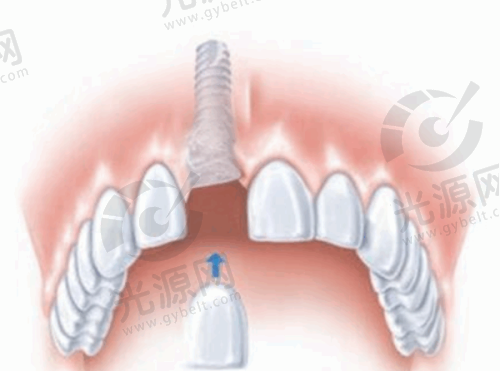

深圳格伦菲尔口腔医院种植牙价格

种植牙是深圳格伦菲尔口腔医院的热门项目之一。2025年,其种植牙价格具有一定的优势。

不同品牌的种植牙价格有所差异:

种植牙品牌 | 价格区间(元起/颗) |

---|---|

韩系进口种植牙 | 2678 |

美国儒伽种植牙 | 4980 |

美国皓圣种植牙 | 3975 |

意大利BB种植牙 | 5980 |

德国贝格种植牙 | 3680 |

瑞典诺贝尔CC种植牙 | 6380 |

瑞士ITI种植牙 | 6580 |

注:以上项目价格仅为参考,具体价格以实际价格为准

此外,在一些活动期间,深圳格伦菲尔口腔医院还会推出优惠套餐。例如,韩国登腾种植牙集采价770元起/颗,种1送1(限首颗);瑞典诺贝尔种植牙原价2.3万元/颗,现直降7000元,1.6万元起/颗。